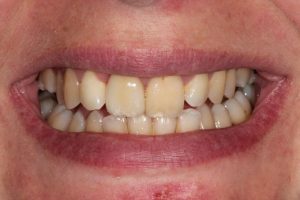

This patient had broken their upper front tooth and the exisitng dental crown had fallen off. The underlying root was unfortunatley irreparable.

The dental root was subsequently removed and an implant placed at the same time. The implant had a temporary crown placedon the same day.

The ‘After’ photos shows the final crown that was made after 3 months. The implant crown was made to match the form and colour of the exisiting teeth to give an overall natural aesthetic finish.